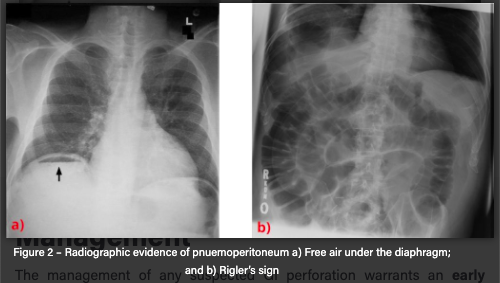

Erect CXR

Can show free air under diaphragm

Rigler’s sign = both sides of the bowel wall can be seen due to free intra-abdominal air acting as an additional contrast